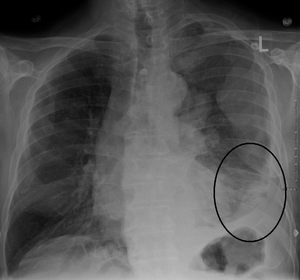

Diagnosing mesothelioma is often difficult because the symptoms are similar to those of a number of other conditions. Diagnosis begins with a review of the patient's medical history. A history of exposure to asbestos may increase clinical suspicion for mesothelioma. A physical examination is performed, followed by chest X-ray and often lung function tests. The X-ray may reveal pleural thickening commonly seen after asbestos exposure and increases suspicion of mesothelioma.[15] A CT (or CAT) scan or an MRI is usually performed. If a large amount of fluid is present, abnormal cells may be detected by cytopathology if this fluid is aspirated with a syringe.[11] For pleural fluid, this is done by thoracentesis or tube thoracostomy (chest tube); for ascites, with paracentesis or ascitic drain; and for pericardial effusion with pericardiocentesis. While absence of malignant cells on cytology does not completely exclude mesothelioma, it makes it much more unlikely, especially if an alternative diagnosis can be made (e.g., tuberculosis, heart failure).[بحاجة لمصدر] However, with primary pericardial mesothelioma, pericardial fluid may not contain malignant cells and a tissue biopsy is more useful in diagnosis.[11] Using conventional cytology diagnosis of malignant mesothelioma is difficult, but immunohistochemistry has greatly enhanced the accuracy of cytology.[بحاجة لمصدر]